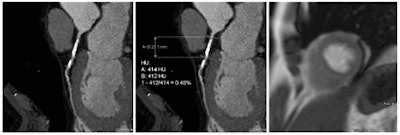

Coronary artery stenosis without hemodynamic significance: CCTA images are at left and center, while MRI (the reference standard for myocardial ischemia) is on the right. Images courtesy of Dr. Rozemarijn Vliegenthart.In the study, each of the 60 asymptomatic patients underwent CCTA and CCO analysis in addition to adenosine perfusion MRI (APMRI). In the analysis of 169 coronary artery stenosis, CCO showed a strong association with functional stenosis at APMRI, but was not correlated to the presence of anatomic stenosis at CCTA, the group reported at ECR 2014.

CCO "estimates the effect of a stenosis by measuring the Hounsfield contrast attenuation before and after a stenosis and corrects this for time using attenuation in the descending aorta," den Dekker explained. "This might substitute for functional imaging and can be added to the anatomical information of CCTA."

To assess the arteries, the group measured luminal CT attenuation values (in Hounsfield Units) in the proximal, middle, and distal segments of each coronary artery, using a dedicated workstation (Aquarius Intuition Edition, TeraRecon). Additional measurements (two proximal and two distal) were performed in arteries with significant (> 50%) lumen stenosis. CCO was then calculated by dividing coronary CT attenuation by descending aorta CT attenuation at equal level.